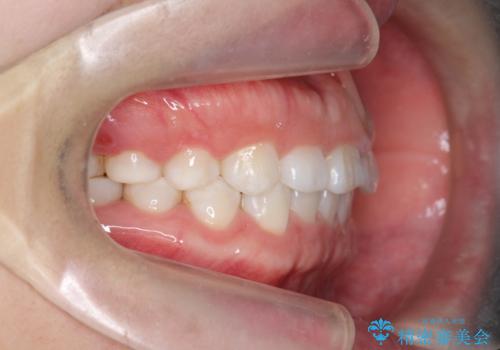

インビザライン 気になるすきっ歯の改善

- 上下顎前歯部の空隙が気になるので治したいと当院にいらっしゃった方の症例です。

非抜歯、インビザラインによる矯正治療により歯と歯の隙間および前歯の上下の隙間を閉じ切りました。